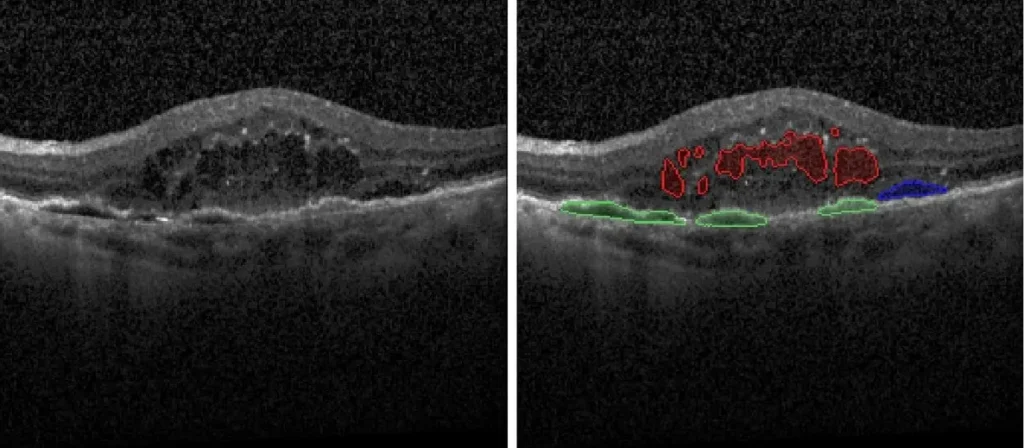

- Fluid Segmentation with Linear, Area, and Volume Quantification:

- Intraretinal Fluid (IRF)

- Subretinal Fluid (SRF)

- Pigment Epithelial Detachment (PED)

- Subretinal Hyper-Reflective Material (SHRM)

Our multimodal overlays combine structural and functional imaging modalities, such as OCT, FAF, and microperimetry, to provide a more comprehensive understanding supported by expert-trained readers who interpret across modalities with deep disease insight.

- Optical Coherence Tomography (OCT):

- Spectral Domain (SD-OCT)

- Swept-Source (SS-OCT)

- Widefield (WF-OCT) / Area of Interest (AOI)